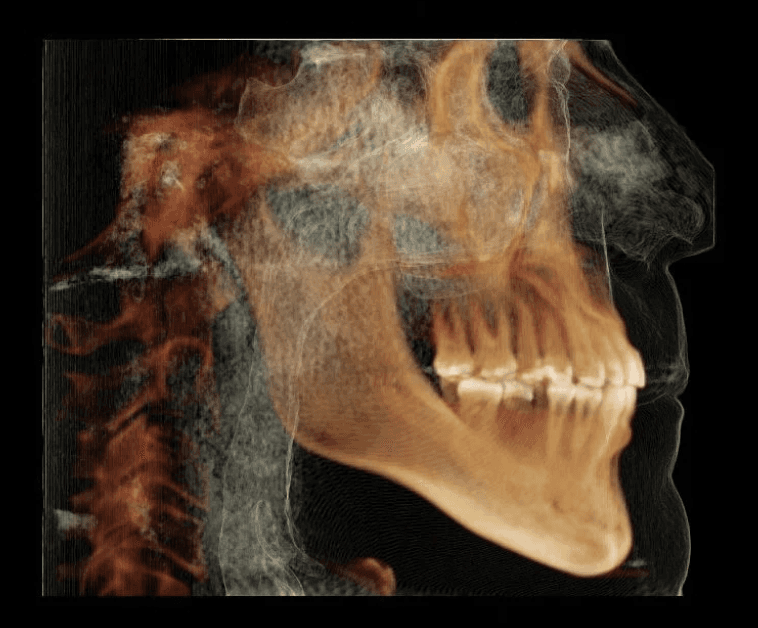

Diagnosis: Anterior crossbite, Class III tendency, moderate crowding/rotations, pre-restorative

X-RAYS